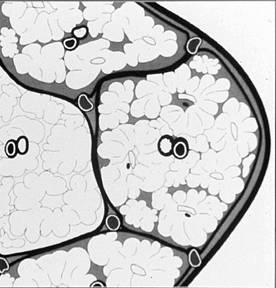

Due to immature lung anatomy & developing immune system, pediatric patients are often particularly susceptible

ADENOVIRUS

Bronchiolar and alveolar damage